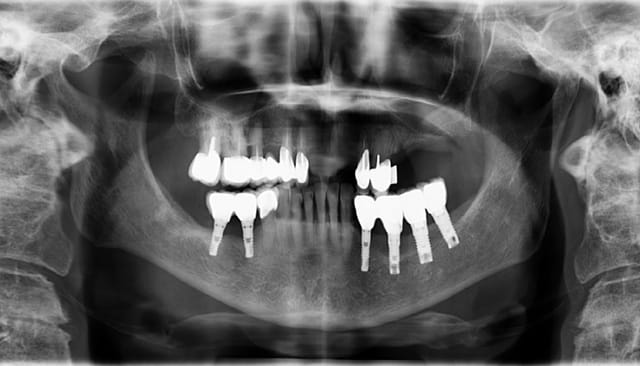

> L'implant mesial n'est pas si mal, aprés qq lithotrities ou autres et la

> réapparition de 2 mm d'os "invisible" elle peut rester sur l'arcade encore

> longtemps.

> En fait c'est le distal, avec une conception disons "particulière", cantilever

> distal + pas de solidarisation qui est le problème.

> S'en débarasser vite pour commencer.

> Ensuite si la patiente veut des molaires, amha implanter en distal de la zone

> d'ostéolyse et faire un bridge 35-37.

Ca c'est une bonne idee. Comme ca on obtient des implants solidarise, ce qui est plus souhaitable apparament.